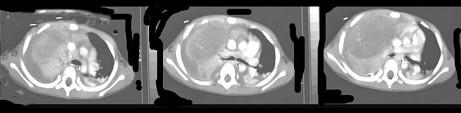

问题 14岁,男,胸闷咳嗽一个月,曾咳出过毛发,CT检查如图,请选择最可能的诊断 ( )

选项 A、畸胎瘤 B、食管囊肿 C、胸内甲状腺肿 D、胸腺囊肿 E、纵隔血肿

答案 A